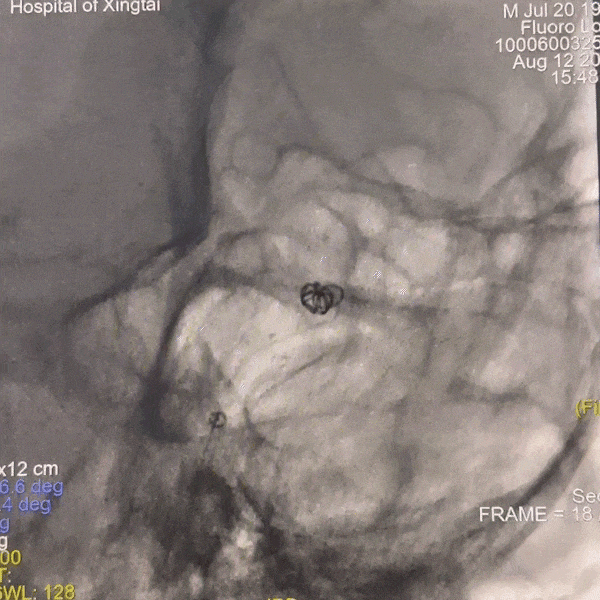

通路建立:患者主动脉弓造影显示Ⅲ型弓,病变为右侧大脑中动脉栓塞,故选择赛诺神畅APEX TRA GC™5F-130 SIM2导引导管同轴长鞘建立通路。

动脉长鞘怎么置入一技之“长”丨经桡及经股困难入路应用赛诺神畅APEX TRA GC™导引导管建立通路病例合集_https://www.jmylbn.com_新闻资讯_第7张

Ⅲ型弓

动脉长鞘怎么置入一技之“长”丨经桡及经股困难入路应用赛诺神畅APEX TRA GC™导引导管建立通路病例合集_https://www.jmylbn.com_新闻资讯_第8张

长SIM2导管成袢

动脉长鞘怎么置入一技之“长”丨经桡及经股困难入路应用赛诺神畅APEX TRA GC™导引导管建立通路病例合集_https://www.jmylbn.com_新闻资讯_第9张

顺利超选入无名动脉

跟进长鞘至右侧颈内动脉,输送068抽吸导管,释放6*30mm 取栓支架。